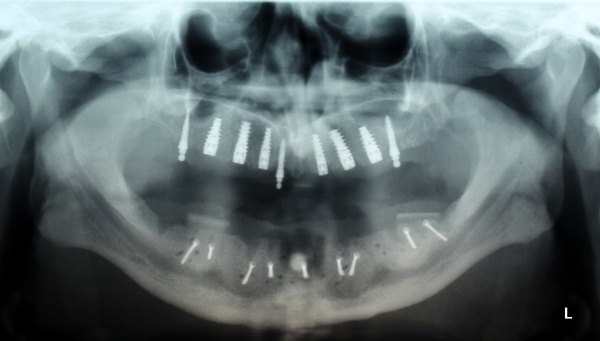

Nach achtwöchiger Ausheilzeit wurde im Mai 2012 eine 3D-Planung der Implantation bei unklarem Knochenangebot durchgeführt. Hierzu erfolgte bei Zahnlosigkeit zur Verankerung der Planungsschablonen im Juni 2012 die Insertion von drei Miniimplantaten im Oberkiefer und drei Miniimplantaten im Unterkiefer. Zur besseren Stabilisierung der schon vorhandenen Totalprothesen wurden Druckknöpfe in die Prothesen eingebracht. Nach Herstellung der Planungsschablonen wurde Ende Juni 2012 eine Denta-CT durchgeführt.

Im Oberkiefer konnten mit der Planungssoftware SkyPlanX der Firma Bredent 6 Implantate mit BoneSplit geplant werden (Abb. 2), im Unterkiefer war eine Implantation aufgrund ungenügenden Knochenangebots nicht möglich.

Im August 2012 erfolgten die 3D-gestützte Implantation (6 Implantate, Firma Nobel Biocare, System Active) im Oberkiefer mit Bone Split sowie eine An- und Auflagerungsosteoplastik vom linken Beckenkamm im Unterkiefer nach Entfernung der Miniimplantate (Abb. 3). Nach komplikationsloser Einheilung wurde im Dezember 2012 die Materialentfernung und Implantation im Unterkiefer (6 Implantate, Firma Nobel Biocare, System Active) durchgeführt (Abb. 4). Die Osseointegration verlief ungestört. Aufgrund der ungenügenden Weichgewebssituation im Unterkiefer erfolgte an jedem Implantat bei Freilegung eine Vestibulumplastik mit Einlagerung einer bioresorbierbaren Membran (Firma Botiss, Mucoderm, Abb. 5 und 6). Die endgültige prothetische Versorgung erfolgte durch den truppenzahnärztlichen Kollegen in der Stammeinheit des Patienten (Zahnarztgruppe Nordholz / SanZ Celle) mit einer gaumenfreien implantatgetragenen Teleskopprothese im Ober- und Unterkiefer, die eine festsitzend-herausnehmbare vollständige stomatognathe Rehabilitation des Patienten ermöglichte (Abb. 7 und 8). Er wurde zum halbjährlichen Recall angehalten.